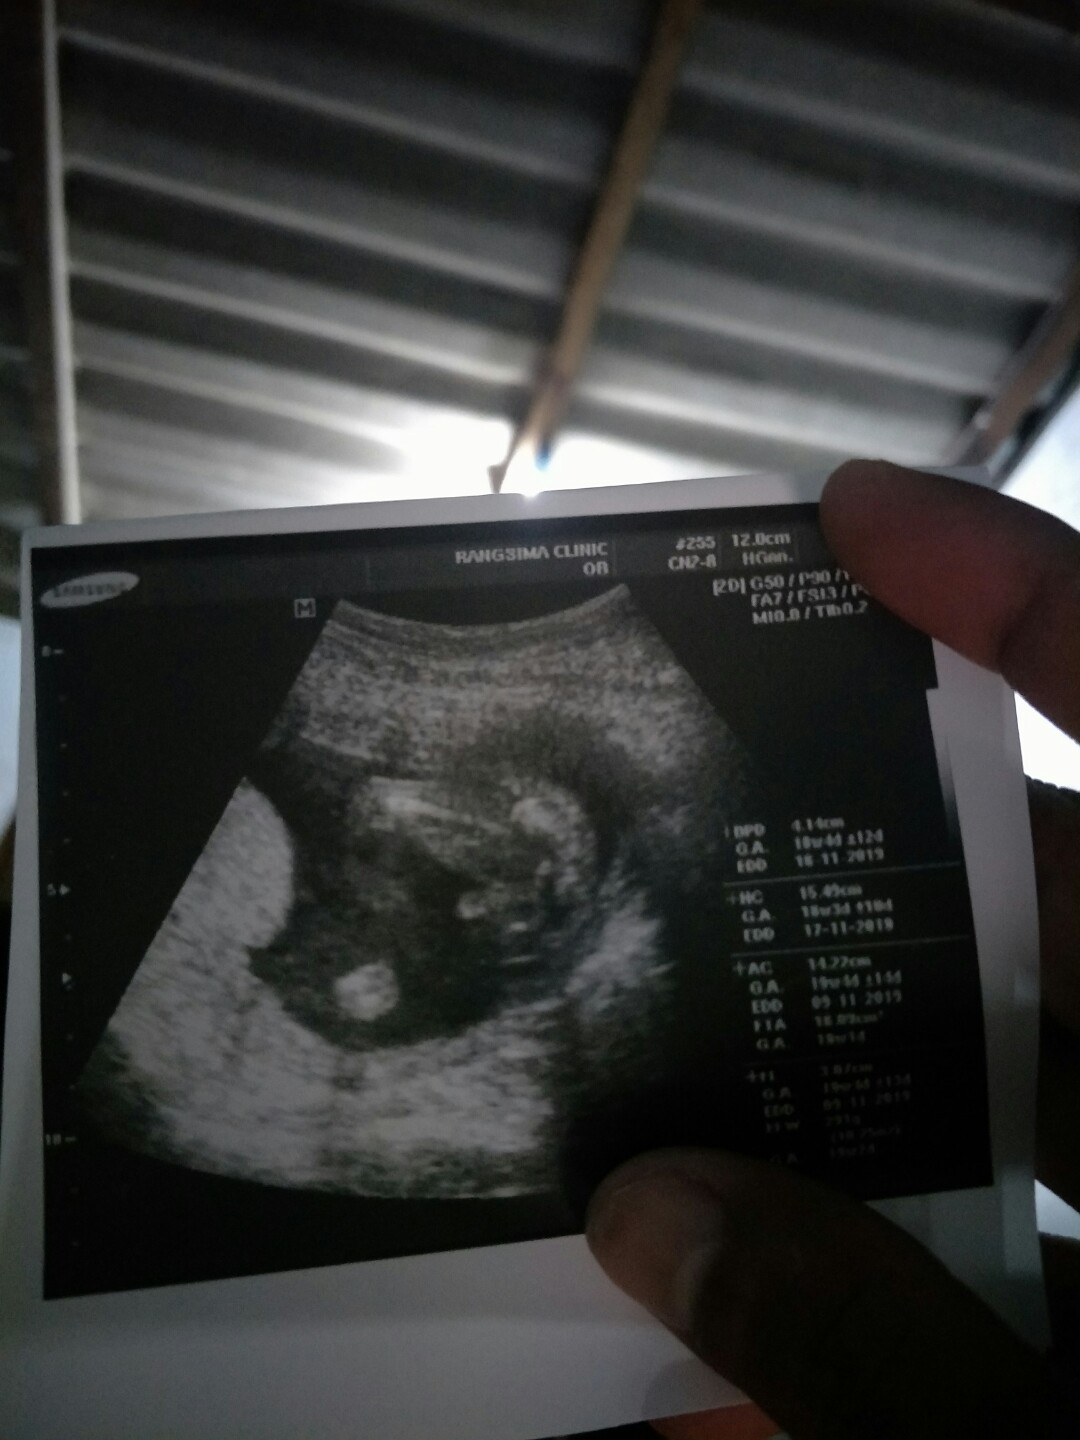

ชายจ้าแม่